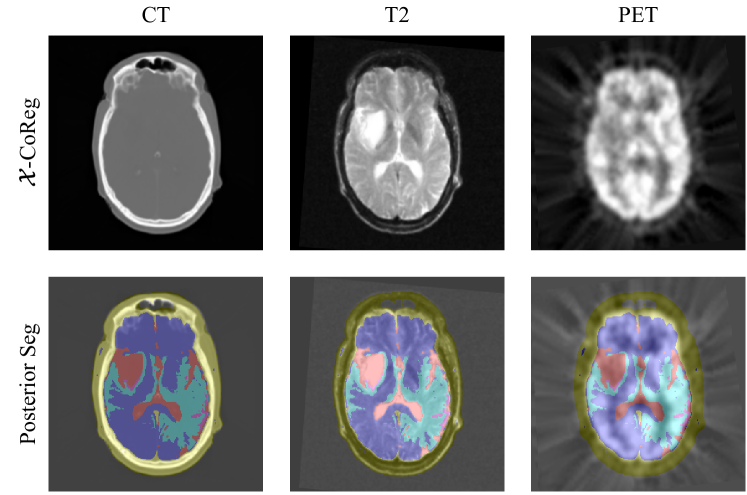

Figure 5: An example of the network architecture for deep combined computing when N=3𝑁3N=3. The encoder \mathcal{E}, the decoders 𝒟ssubscript𝒟𝑠\mathcal{D}_{s} and 𝒟rsubscript𝒟𝑟\mathcal{D}_{r}, and the bottleneck are composed of residual convolutional blocks. Domain-specific batch normalization layers are indicated with different colours. Cardiac structures, i.e. myocardium, left ventricle (LV) and right ventricle (RV), are rendered as contours.

Fig. 5 presents the network architecture for deep combined computing. The network is composed of an encoder \mathcal{E}, a bottleneck, a segmentation decoder 𝒟ssubscript𝒟𝑠\mathcal{D}_{s} and a registration decoder 𝒟rsubscript𝒟𝑟\mathcal{D}_{r}. They comprise multiple levels of residual convolutional blocks (RCBs) and residual connections between the encoder and decoder [33]. The convolutional layers of the block in the l𝑙l-th level have C2l1𝐶superscript2𝑙1C\cdot 2^{l-1} feature maps, for l=1,,LR𝑙1subscript𝐿𝑅l=1,\dots,L_{R}, with C𝐶C a user-defined constant.

The task of segmentation and registration are often regarded related. Segmentation aims to assign pixel-wise semantic labels to the input image, while registration seeks to find structural and spatial correspondences between input images. Thus, when designing a neural network to make predictions, we believe to some extent there could be shared representations utilized by both of the tasks. Therefore, the proposed network has a shared encoder and two separated decoders for the two tasks.

To extract modality-invariant features, the convolutional layers of the encoder \mathcal{E} are shared across modalities, while domain-specific batch normalization layers seek to disentangle structural codes from the appearances of multimodal input images [34]. The segmentation decoder 𝒟ssubscript𝒟𝑠\mathcal{D}_{s} is then fed with the modality-invariant features to predict the segmentation probability maps 𝝆^^𝝆\widehat{\bm{\rho}} for each image.

The extracted features of each image are also fused by an abstraction layer that computes their first and second moments [35]. The fused feature maps then pass through the registration decoder 𝒟rsubscript𝒟𝑟\mathcal{D}_{r} to predict the desired spatial correspondences ϕbold-italic-ϕ\bm{\phi} in the form of dense displacement fields.

Moreover, the network parameters for segmentation and registration are optimized alternately so that the improvement of one task can benefit the other. We chose to alternate training between the two branches because in Eq. 42 the term H𝒁[2](𝒀^jϕj)subscript𝐻superscript𝒁delimited-[]2subscript^𝒀𝑗subscriptitalic-ϕ𝑗H_{\bm{Z}^{[2]}}(\widehat{\bm{Y}}_{j}\circ\phi_{j}) is computed using both branches. That is, 𝒀^jsubscript^𝒀𝑗\widehat{\bm{Y}}_{j} is predicted by the segmentation branch while ϕjsubscriptitalic-ϕ𝑗\phi_{j} is predicted by the registration branch. Therefore, to avoid interference in two branches, like the situation where the registration branch may seek to compensate for errors in the segmentation prediction, it could be better to alternate the training for the two branches.